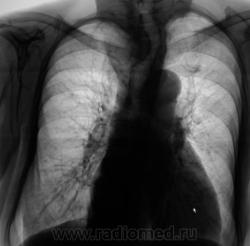

Экспансивно растущее об"емное образование верхнего средостения, неоднородной структуры за счет включений кальция. Состоит ли на учете у эндокринолога? Похоже на "ныряющий" зоб.

На учете не состоит. О патологическом процессе ранее было ничего не известно. "Выцепили" сегодня, сегодня и дообследовали.

Скопически не смотрел, шел "большой поток". Пациент женского пола - "божий одуванчик", весьма преклонного возраста, лежит в терапии с диагнозом "ИБС". Хотя, после Вашего коммента появилась мысль - а почему-бы не взять за экран? Пациентка "под боком", в отделении.

Думаю, что не "ныряющий", а конкретно "нырнувший", да там и "заночевавший" загрудинный зоб, включения кальция ничего хорошего не сулят. Согласен - УЗИ с, при необходимости,  биопсией.

Следует провести R-скопию, а желательно ещё и с рентген-контрастным веществом.